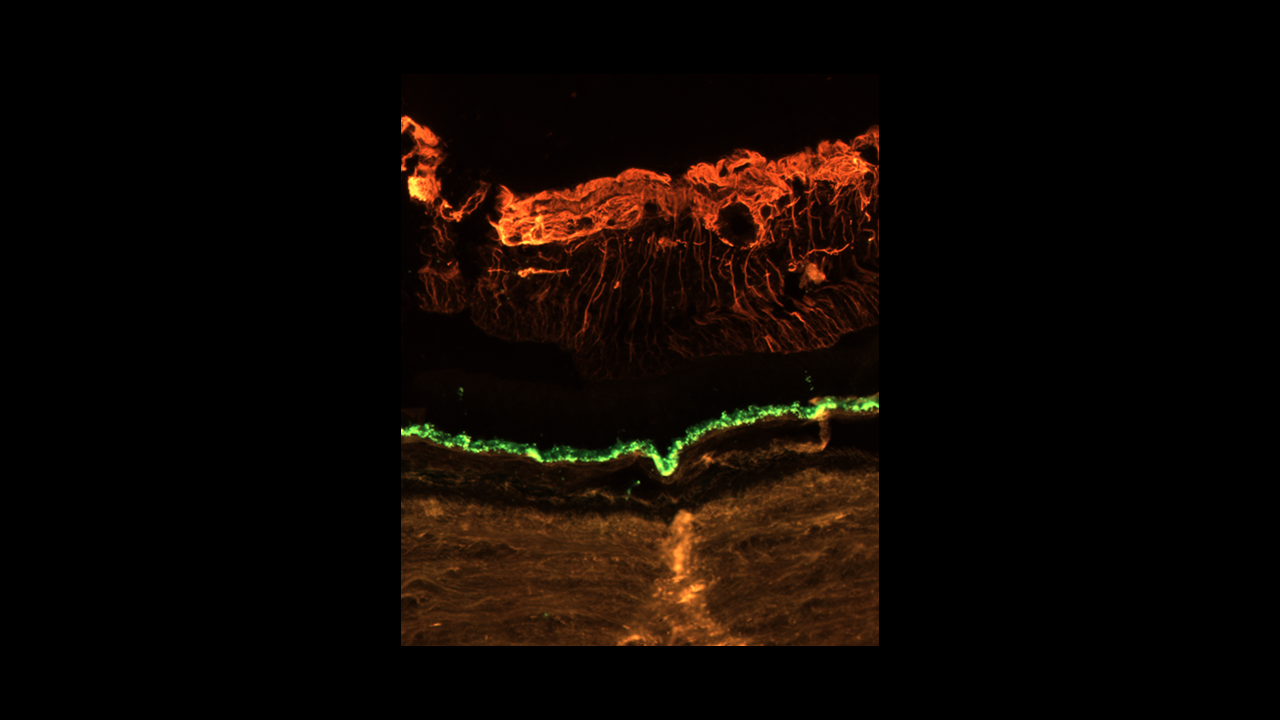

MERFISH image of articular cartilage courtesy of David Rowe's lab at UConn